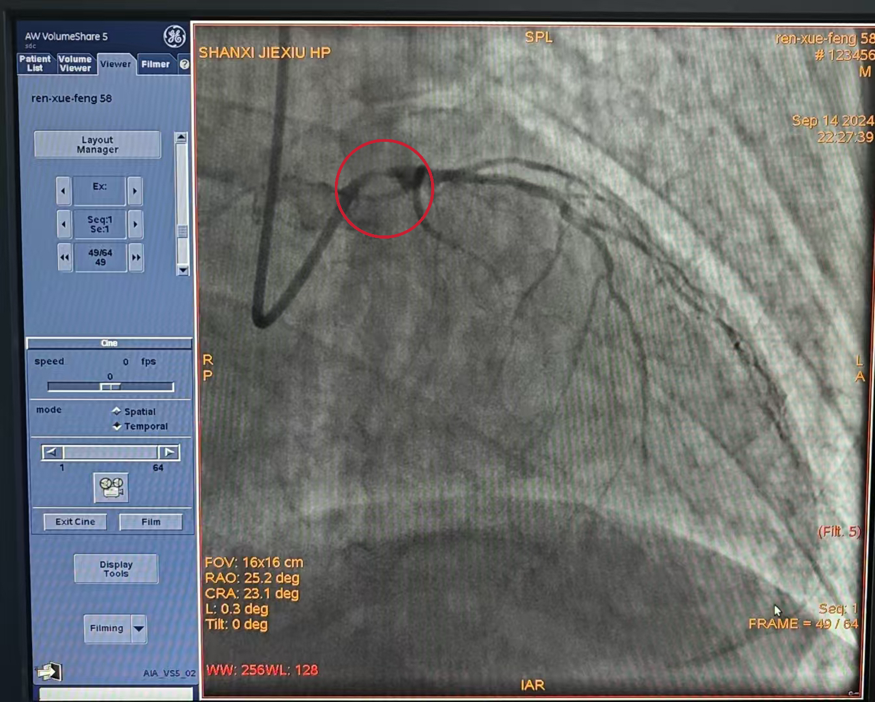

患者病情危急,手术过程复杂且凶险,在心内科手术医师及介入团队配合下仅仅使用20分钟即顺利完成整台手术,于左主干到前降支植入支架一枚,患者胸痛症状明显改善。